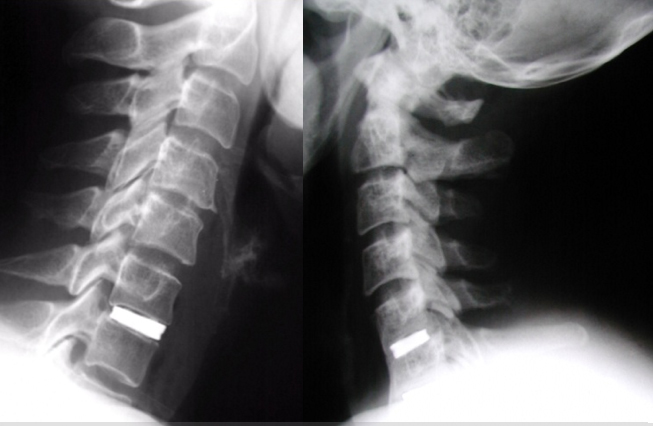

Las siguientes imagenes corresponden a un estudio funcional (flexion y extension). Notese como el bloque marcado con un rectangulo se mueve solidariamente y la distancia interespinosa no aumenta apenas. Este estudio indica que se ha logrado una buena estabilizacion primaria.